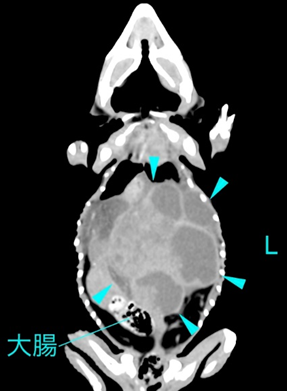

コンピュータ断層撮影(CT)検査の保定

近年、マルチスライスCTの高速化に伴い、無麻酔または軽い鎮静下での撮影が可能となっています。小型~中型のトカゲでは容器に入れて、隙間をティッシュやタオルで前後を挟んで動きを制限する方法が有効です。放射線透過性のアクリル板や硬質発泡スチロールの上に、紙テープで四肢と尾を固定することもあります。グリーンイグアナでは迷走神経反射を併用することもありますが、ガントリーの回転音や振動で覚醒する可能性があるため、完全な不動化は期待できません。麻酔に伴う呼吸抑制のリスクがない反面、体動によるモーションアーチファクトが発生しやすく、画質が低下する場合があります。